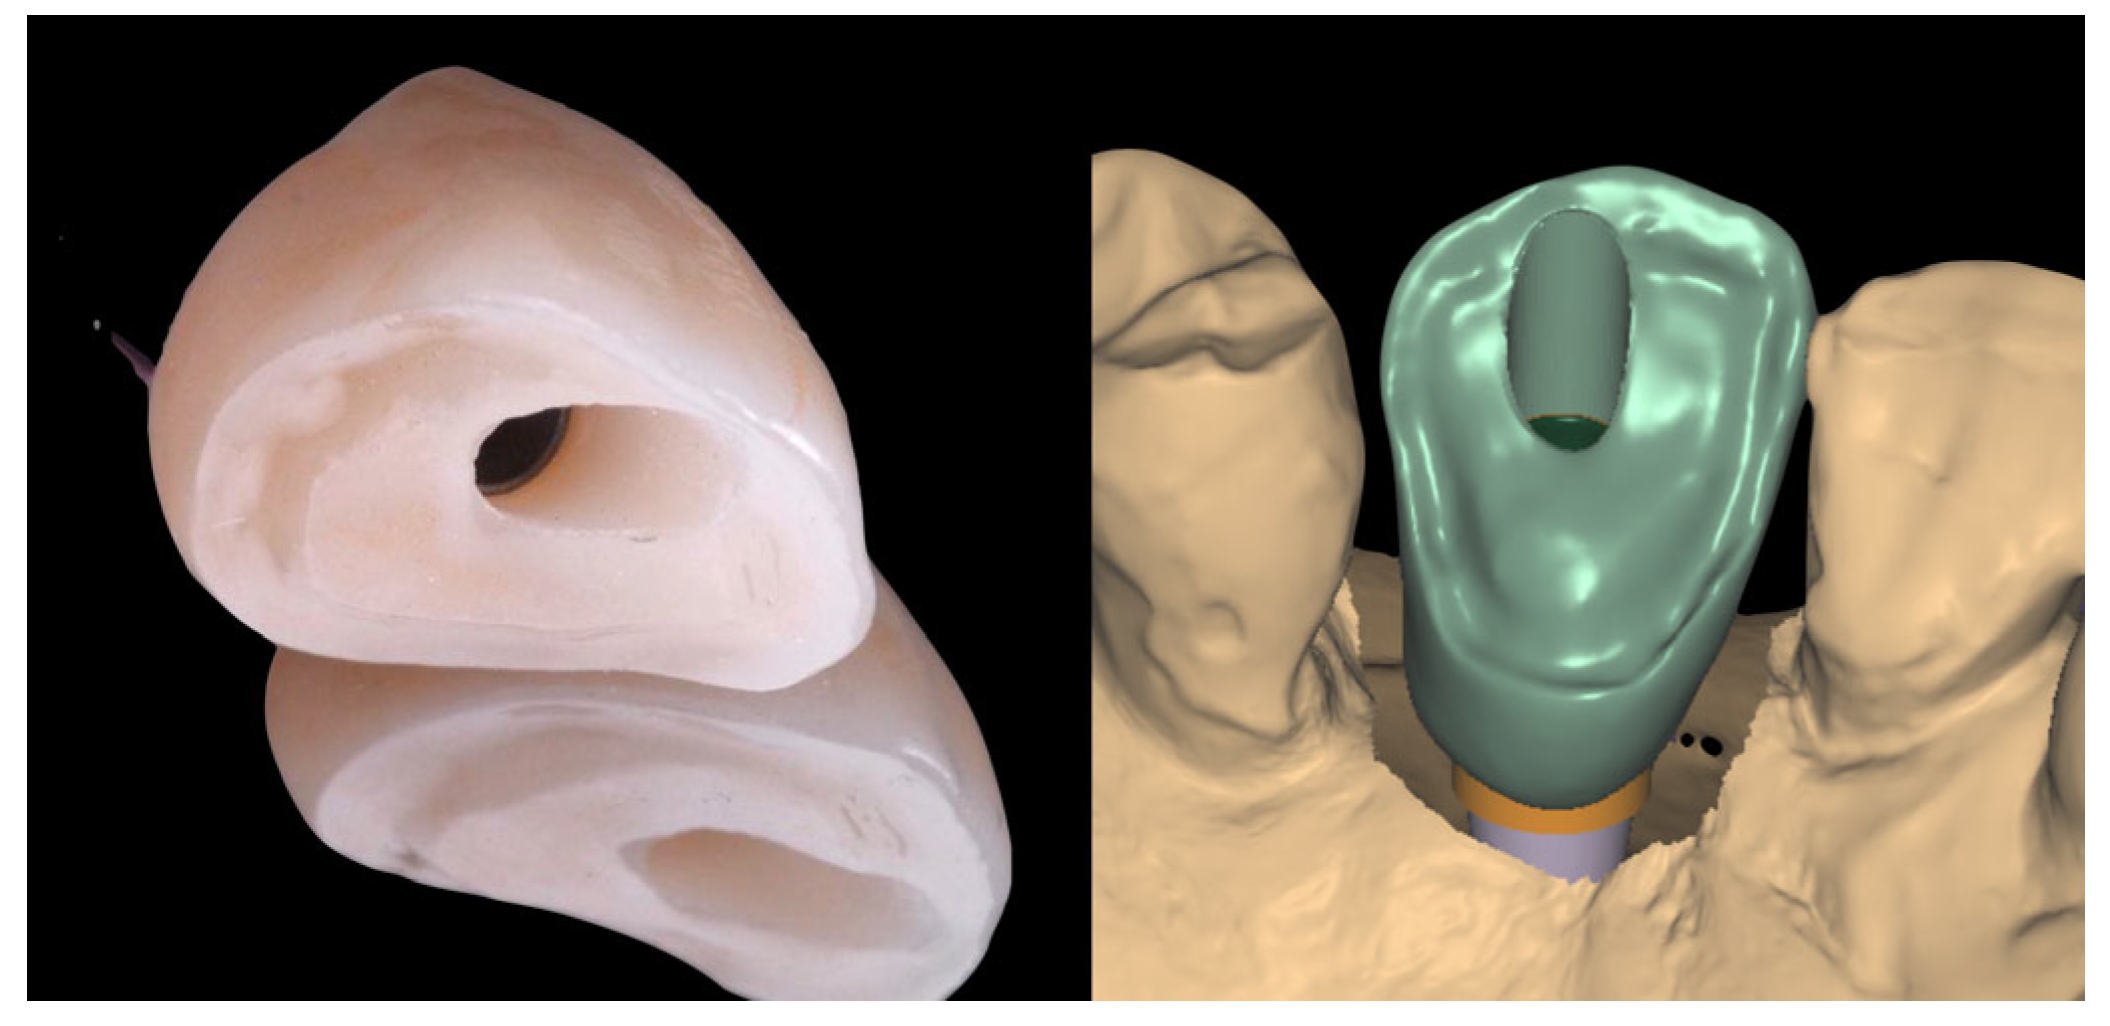

2.3. Laboratory Procedure